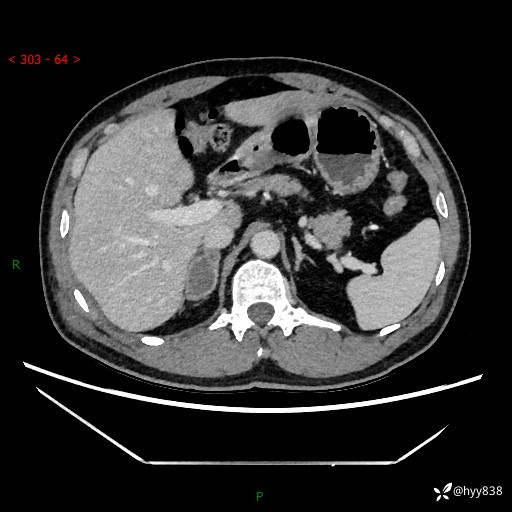

现病史:患者9月4日摔伤在深圳市宝安区中心医院行CT检查提示右侧肾上腺区结节(38*27mm),复查B超提示右侧肾上腺区可见一61*24mm异常低回声团,建议进一步检查。进一步完善增强CT后提示:右侧肾上腺区肿块及周围渗出改变,大致同前,考虑肾上腺腺瘤,不除外瘤内出血可能,否认阵发性头晕、头痛、出汗、乏力等不适,门诊以“ 右侧肾上腺肿瘤”收入住院。 起病来,患者精神、食欲、睡眠可,大便通畅,小便如上述,体力体重无明显改变。

肾上腺CT平扫

增强(动脉期+静脉期)